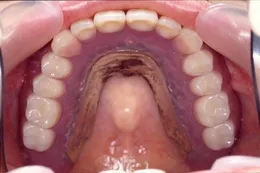

当院での部分入れ歯の特徴:残っている歯を診査し徹底した治療を行います。歯を失い始めたらもうあるがままでは健康な状態を保てません。抜いて傷が治ったらすぐに入れ歯を入れることは他の歯の寿命も短くしてしまうかも知れません。

金具がかかる歯の整備をします。おもにかぶせ物を使って環境整備を行います。

(部分入れ歯を入れるためには残っている歯に前処置を行い整備が必要となります。)

(残っている歯にかぶせ物等で整備しておくとぴったりと入れ歯が適合して『動かない入れ歯』を装着することができます。)